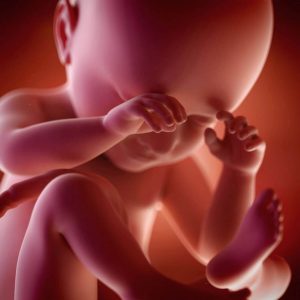

단지 엄마의 심장 박동과 엄마 배 가까이서 들리는 음악뿐 아니라, 아기는 자라면서 끊임없이 엄마로부터 메시지를 받는다. 이 시기에 아기는 태반을 통해 화학 신호를 받는다. 그리고 이 신호들은 엄마의 감정 상태도 포함하고 있다.

만약 엄마가 몹시 슬프거나 매우 우울하면 아기도 똑같이 느낀다. 그리고 이 정서적 상태는 아기의 일생 동안 아기의 발달에 상당한 영향을 준다. 장기적으로 우울증 증세을 앓고 있는 엄마는 신경이나 정신적으로 문제가 생길 수도 있다고 한다.

게다가 앞선 연구를 진행한 과학자들은 임신 기간의 불안 증세(흔히 우울증 증세)를 보이는 엄마의 아이들은 두뇌 구조에 특정한 차이를 가지고 있다는 사실을 발견했다. 하지만 여전히 임신 기간 엄마의 우울증 증세가 아이에게 장기적으로 정확히 어떤 영향을 주는지 알아보기 위해서는 더 많은 연구가 필요하다.